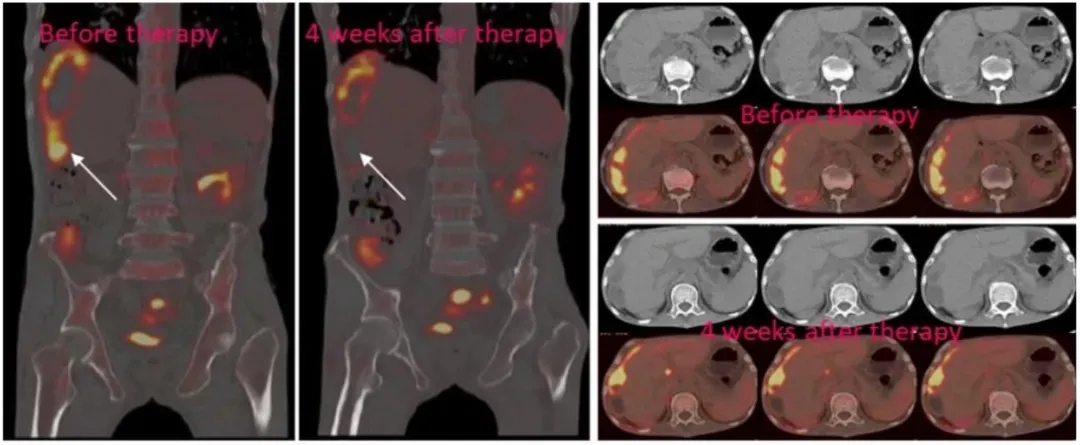

2、另1例在入组前就已发生肝转移的患者,在回输CAR-NK细胞(腹腔内灌注+超声引导下,瘤内经皮注射)后,PET-CT显示,治疗后肝脏病灶呈现完全代谢反应(详见下图)。

3、除此之外,这3例患者在治疗过程中,均未出现3级以上的不良反应(详见下图)。

图4 3号患者经NKG2D CAR-NK治疗后,肝转移病灶的PEC-CT对比

基于上述研究结果,初步证明了NKG2D mRNA CAR-NK细胞,在治疗转移性结直肠癌方面的安全性及可行性,为晚期结肠癌患者提供了一种新的免疫治疗选择!